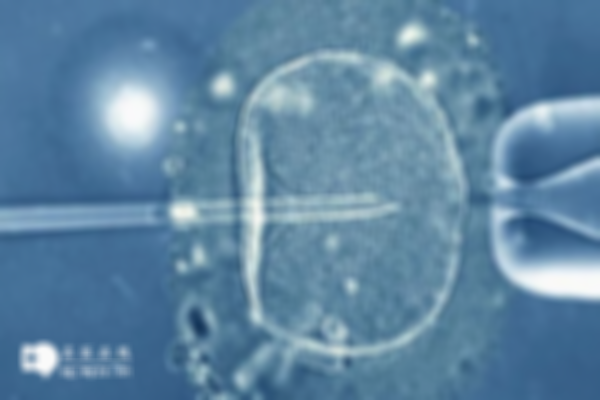

體外受精和胚胎移植可以幫助不孕夫婦懷孕。解基女性接受排卵誘導藥物治療,本原促進卵巢發育,釋放多個卵泡。然后,在手術室收集成熟的卵子,并向男性提供體外受精的免費精子。高質量的胚胎經過培養和篩選后被選擇并移植到女性子宮中。最后,如果胚胎成功植入并發展成正常的孕囊和胎兒,試管嬰兒的成功率就會提高。

美國醫生和技術人員在手術操作方面有豐富的經驗和專業知識。采用先進的設備和技術進行卵子采集、受精和胚胎移植等關鍵步驟,以確保手術過程的安全。